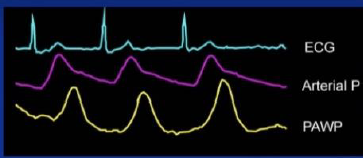

Criança de 6 anos de idade na UTI devido a quadro de choque. Ao monitorizá-la, observase o traçado ilustrado a seguir.

Considerando a curva de PVC, qual é a patologia menos provável de ser encontrada nesse paciente?

Provas